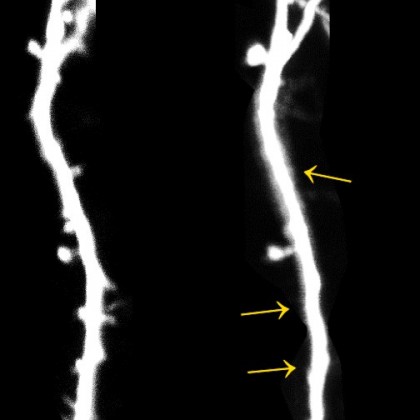

foto: Neuronul unui șoarece: - Între cele două imagini sunt 14 zile, timp în care animalul a fost stresat timp de 10 zile. Procesele etichetate care conțin sinapse s-au pierdut în acest timp. © Figure: AG Stein / University of Bonn

Explicația producerii acestui fenomen pornește de la microglii, ce au rolul de a digera agenții patogeni și elimina celule bolnave. Acestea, atunci când subiectul este expun la stres, atacă zone de contact dintre neuroni denumite sinapse.

În mod normal, atunci când învățăm ceva nou, între neuronii noștri se formează noi legături. În schimb, rezultatele studiului au arătat că, în condiții de stres, numărul de șoareci care au reușit să învețe să-și procure hrana cu un singur membru a fost o treime din cel reprezentat de șoarecii ținuți în medii neutre, având aceeași sarcină.